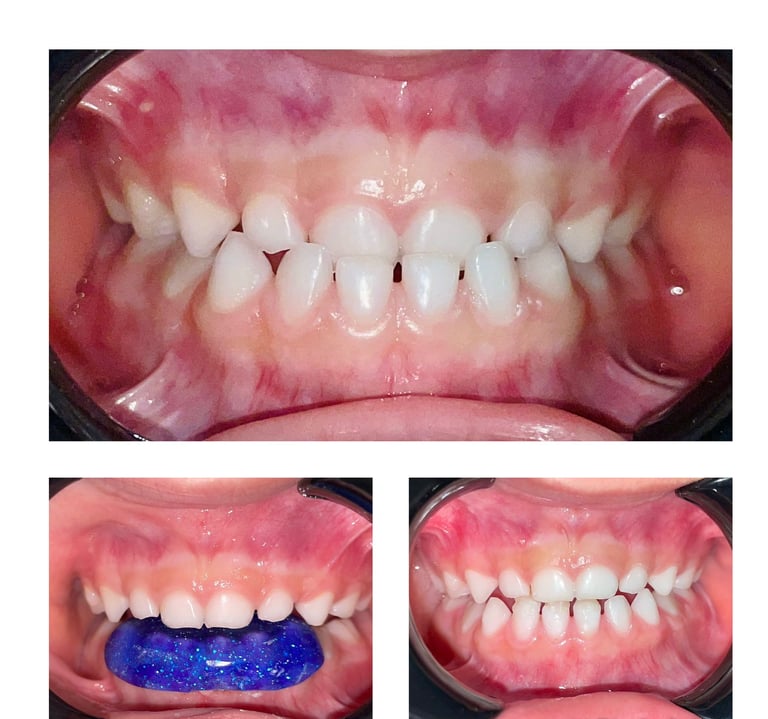

Odontopediatría

La odontopediatría es la especialidad dental dedicada a el cuidado, tratamiento y prevención de las lesiones bucales en niños y adolescentes. Nuestro enfoque es brindar un ambiente amigable y acogedor, adaptado a las necesidades de los pequeños pacientes, para asegurar una experiencia cómoda y libre de miedo. Ofrecemos controles preventivos, limpieza, tratamiento de caries, sellantes y orientación en hábitos de higiene bucal. En nuestra clínica, promovemos una sonrisa saludable desde temprana edad, formando buenos hábitos que perdurarán toda la vida.